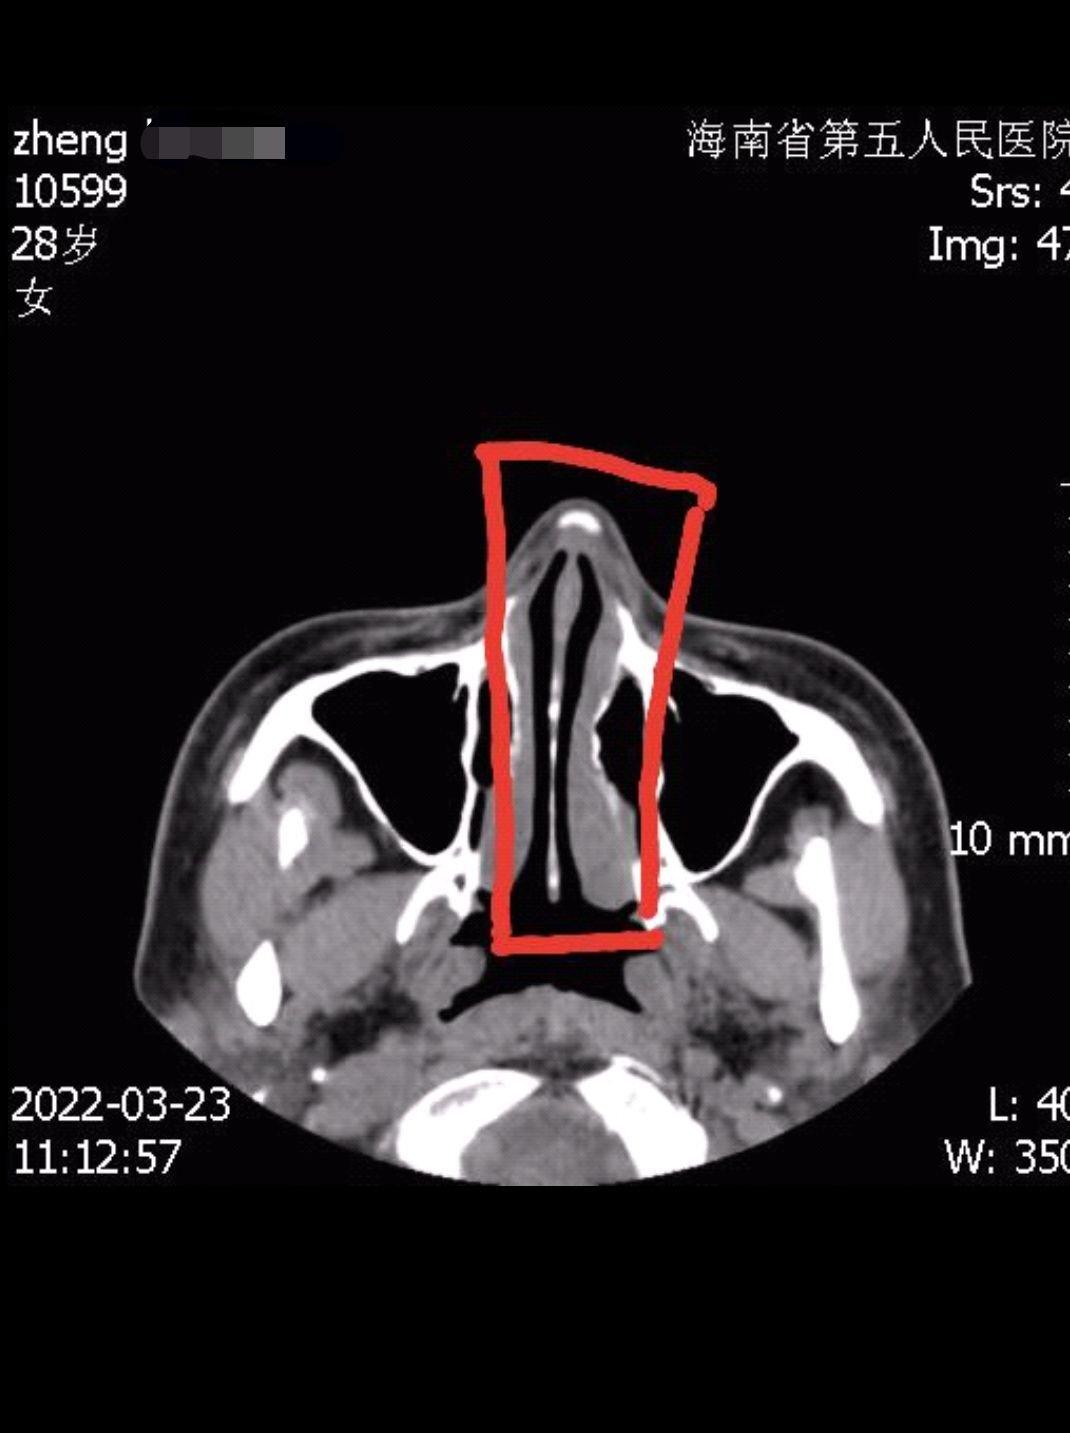

鄭女士在整完后,身邊人提醒她,鼻子怎么變歪了,她對(duì)著鏡子細(xì)細(xì)端詳,感覺鼻子確實(shí)被整歪了,為了證實(shí)不是眼神和角度問題,她便去海南省第五人民醫(yī)院拍片。“人的主觀視覺可能會(huì)看走眼,但機(jī)器固定拍攝,騙不了人,片子拍出來后,海南省第五人民醫(yī)院的醫(yī)生明確告訴我,鼻子里面放的假體沒有放正,歪了3毫米左右,所以鼻子是歪的。”鄭女士指著鼻子的X光片說,這肉眼可見假體是歪斜的,無論是從側(cè)面、正面,還是上面,任何角度都是歪的?!拔椰F(xiàn)在是欲哭無淚,只想趕快湊夠錢,把假體取出來,再也不因?yàn)閯e人制造的面容焦慮而去整形了?!编嵟堪脨赖卣f道。

當(dāng)天,記者實(shí)地走訪海南優(yōu)姿妍醫(yī)療美容門診部,現(xiàn)場(chǎng)有數(shù)名醫(yī)美消費(fèi)者在準(zhǔn)備整形,為了不影響該醫(yī)療美容門診部日常運(yùn)行,記者便在一間辦公室進(jìn)行采訪。起初,海南優(yōu)姿妍醫(yī)療美容門診部一名主管接受采訪,對(duì)方告訴記者,機(jī)構(gòu)負(fù)責(zé)人因身體問題,不方便出面接受采訪,隨后查看了鄭女士提供的X光片子,表示沒看出假體歪斜。在鄭女士指出歪斜處后,該主管這才承認(rèn)了歪斜事實(shí)。